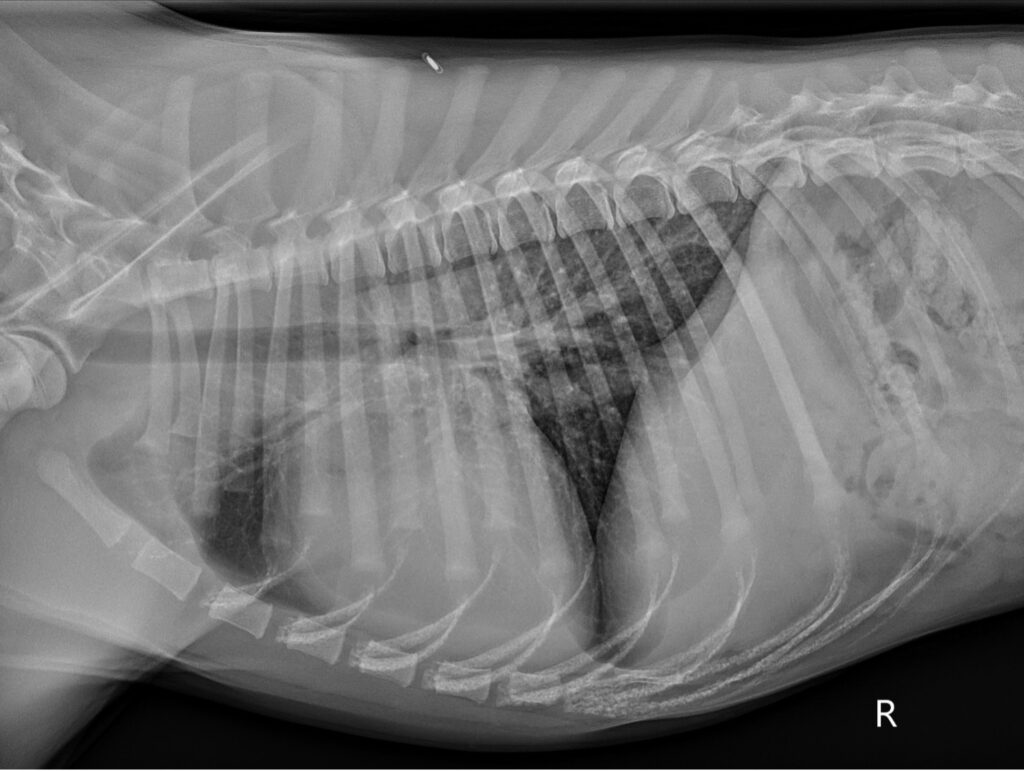

Teşhiş için de uzman bir doktor kalp atışını dinlemelidir. Bunun sonucunda kalpteki problemden şüphelenilir. Ekokardiyografi ile de bebeğin kalbi dikkatlice incelenir ve bunun sonucunda teşhis konulur.